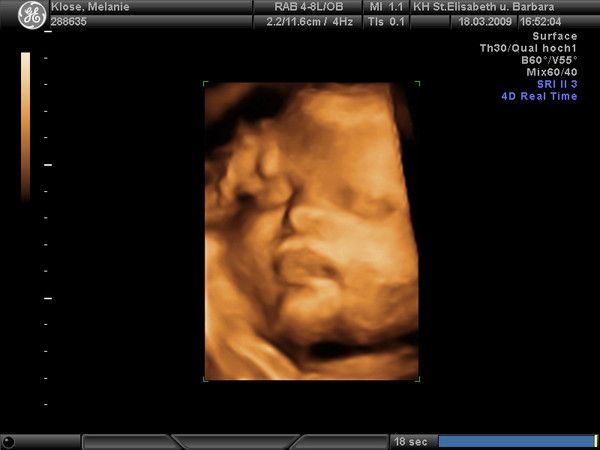

Club-Fotos

Hier sehen Sie alle Fotos dieses Clubs.